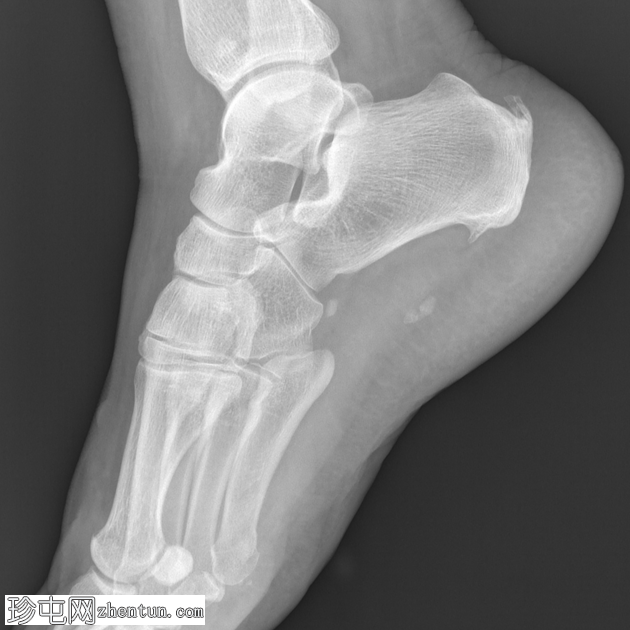

X光片

侧位

正位

沿足底筋膜走行可见两处相邻的小钙化灶。跟腱附着点病和足底跟腱骨赘形成。腓籽骨副骨。

一名中年女性,既往有软组织损伤史,出现足底筋膜钙化。